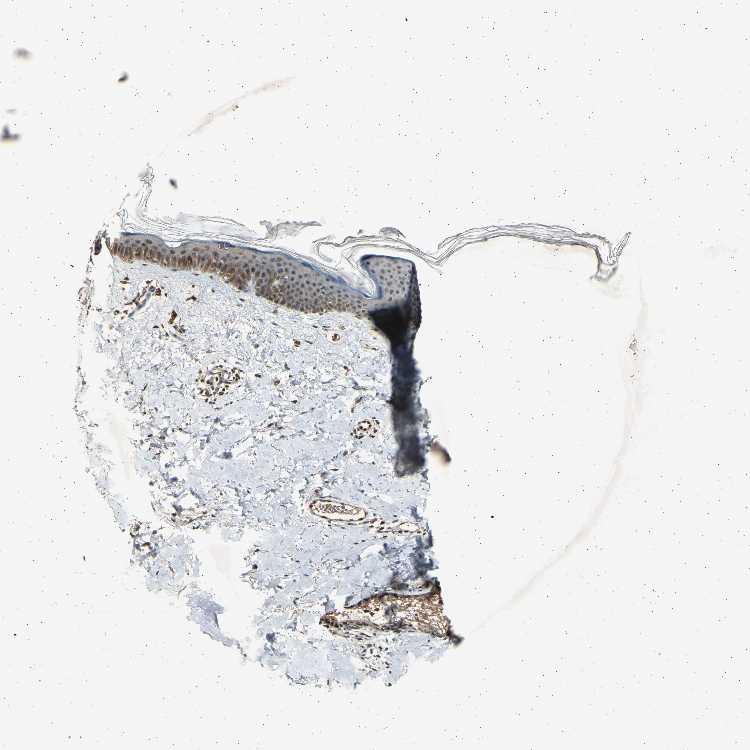

SKIN 1 - Antibody stainingi

Antibody staining in the annotated cell types in the current human tissue is reported as not detected, low, medium, or high, based on conventional immunohistochemistry profiling in selected tissues. This score is based on the combination of the staining intensity and fraction of stained cells.

Each image is clickable and will lead to virtual microscopy that enables deeper exploration of all samples and also displays staining intensity scores, fraction scores and subcellular localization as well as patient and tissue information for each sample.

Antibody HPA003216

Langerhans Medium

Fibroblasts Low

Keratinocytes Medium

SKIN 2 - Antibody stainingi

Epidermal cells Medium